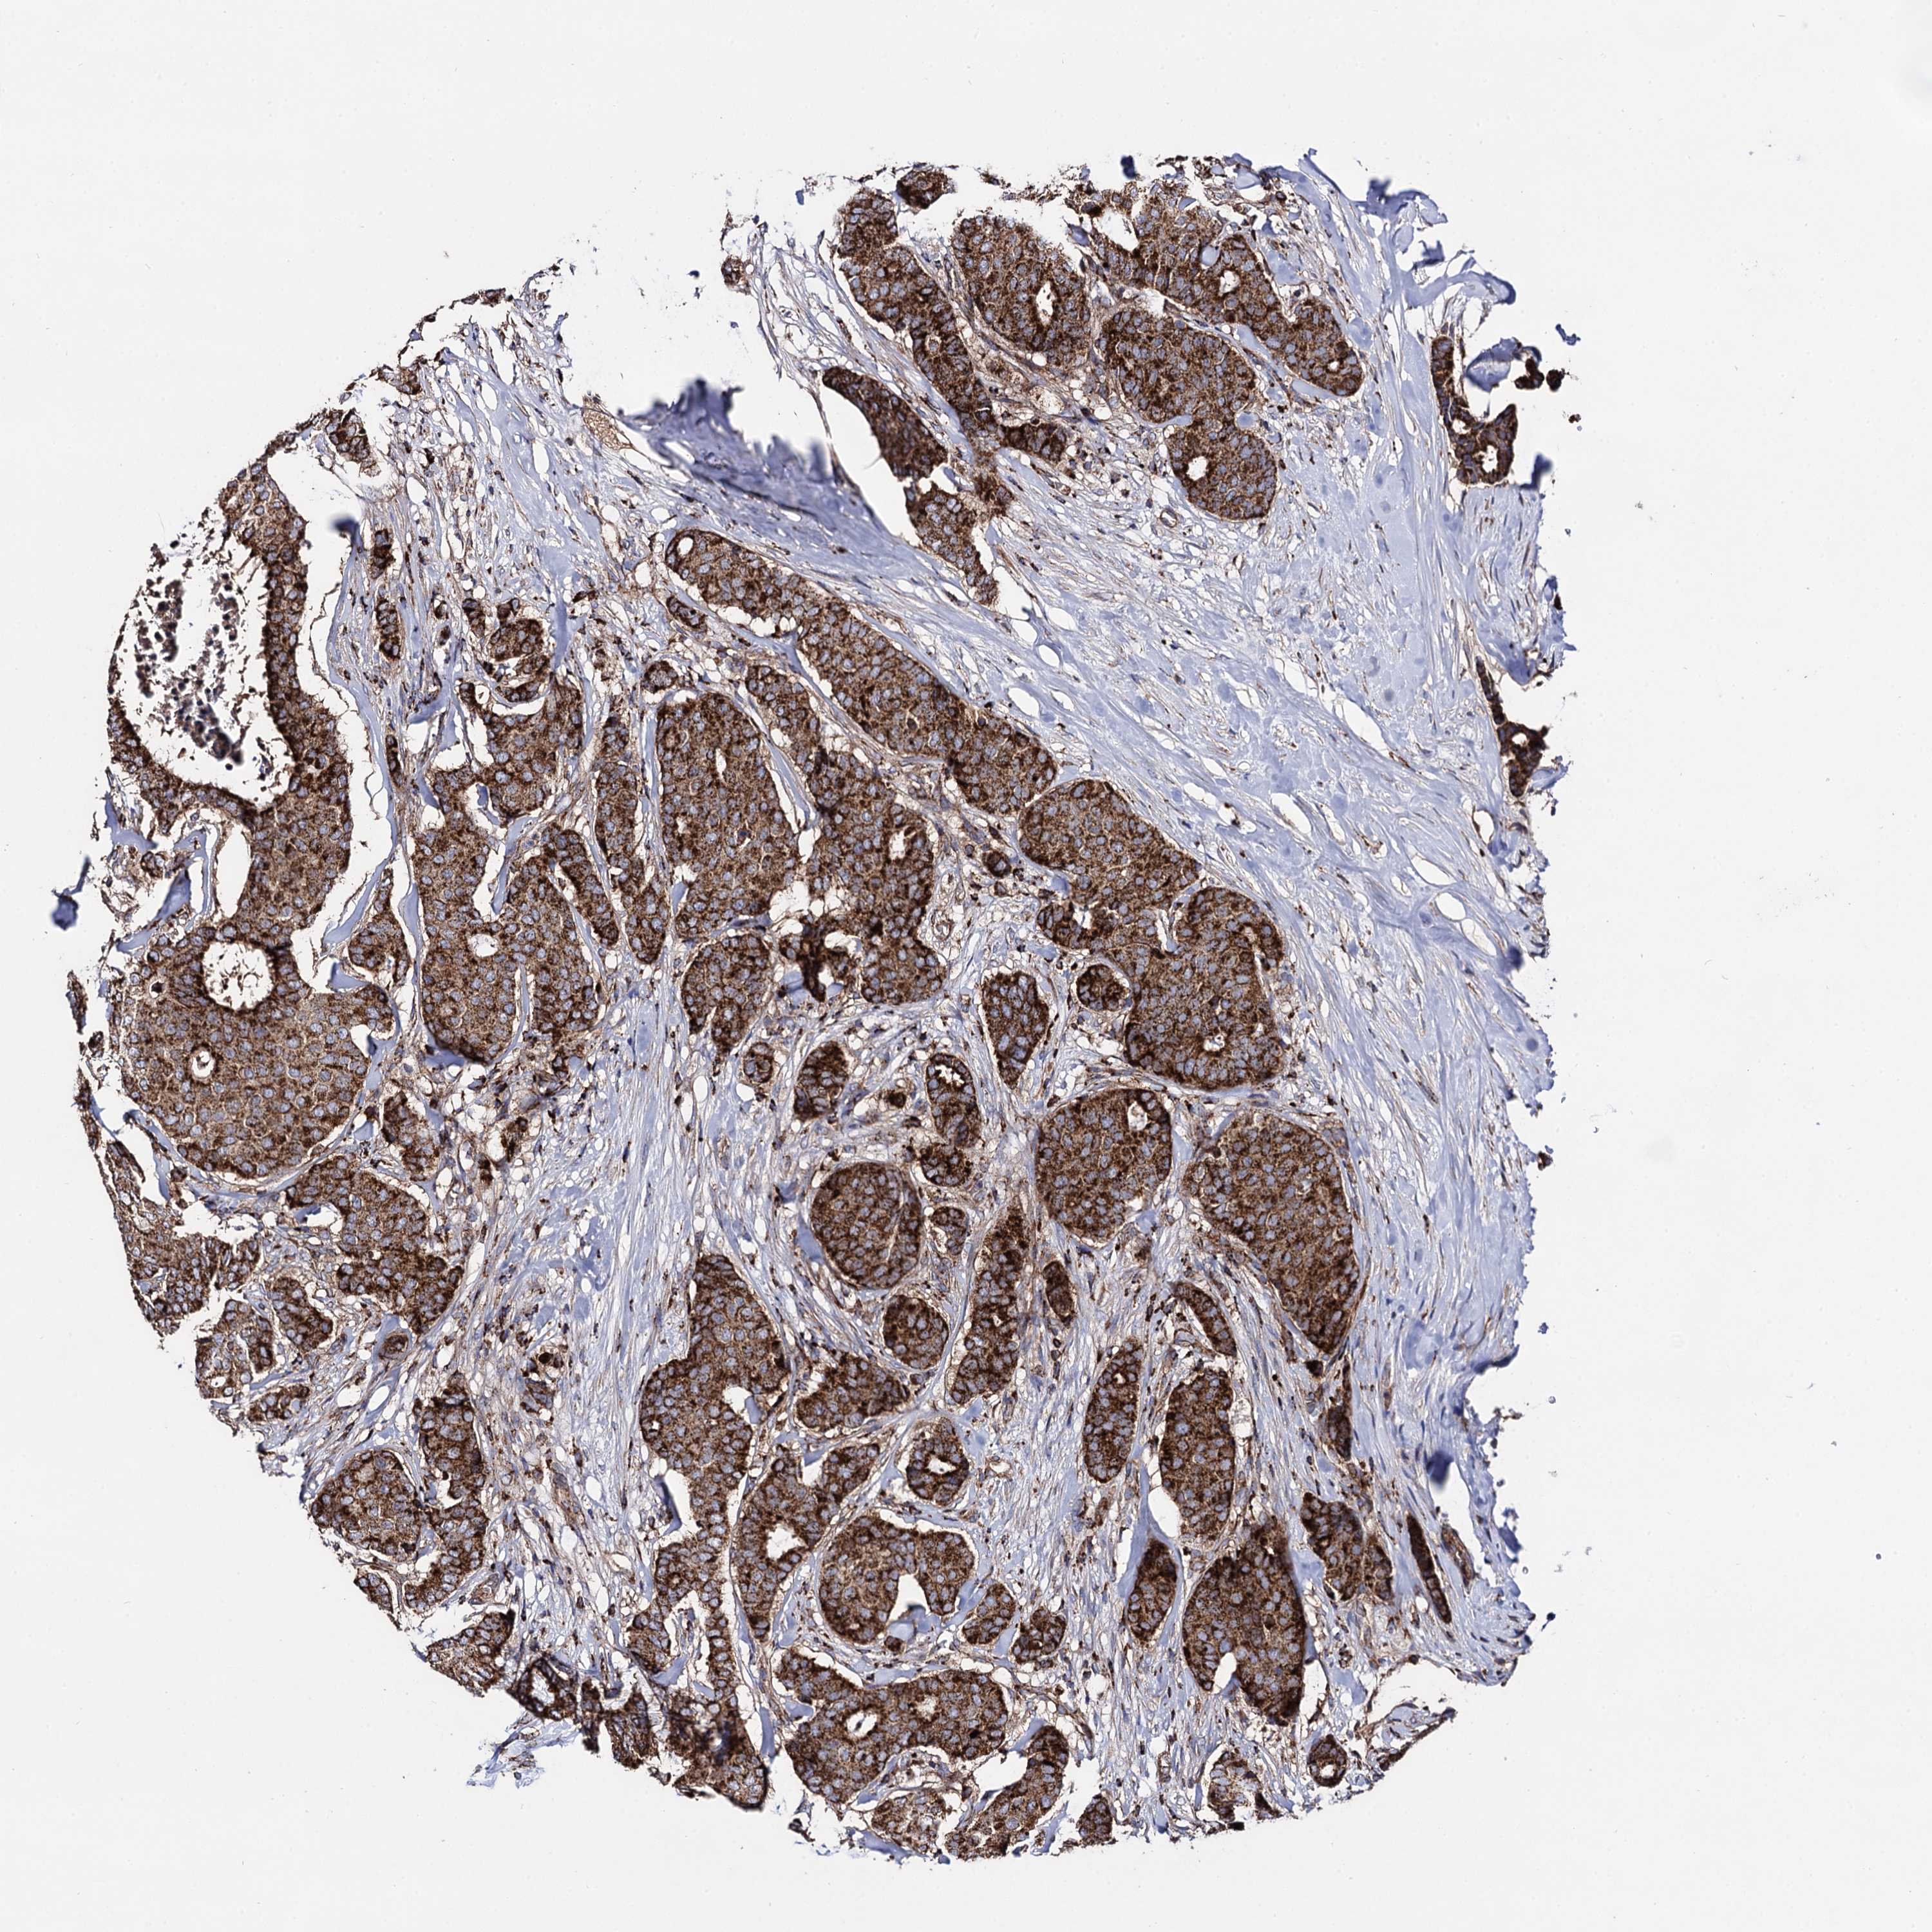

CANCER BREAST CANCER Show tissue menu

BRCA TCGA BRCA VALIDATION PROTEIN EXPRESSION